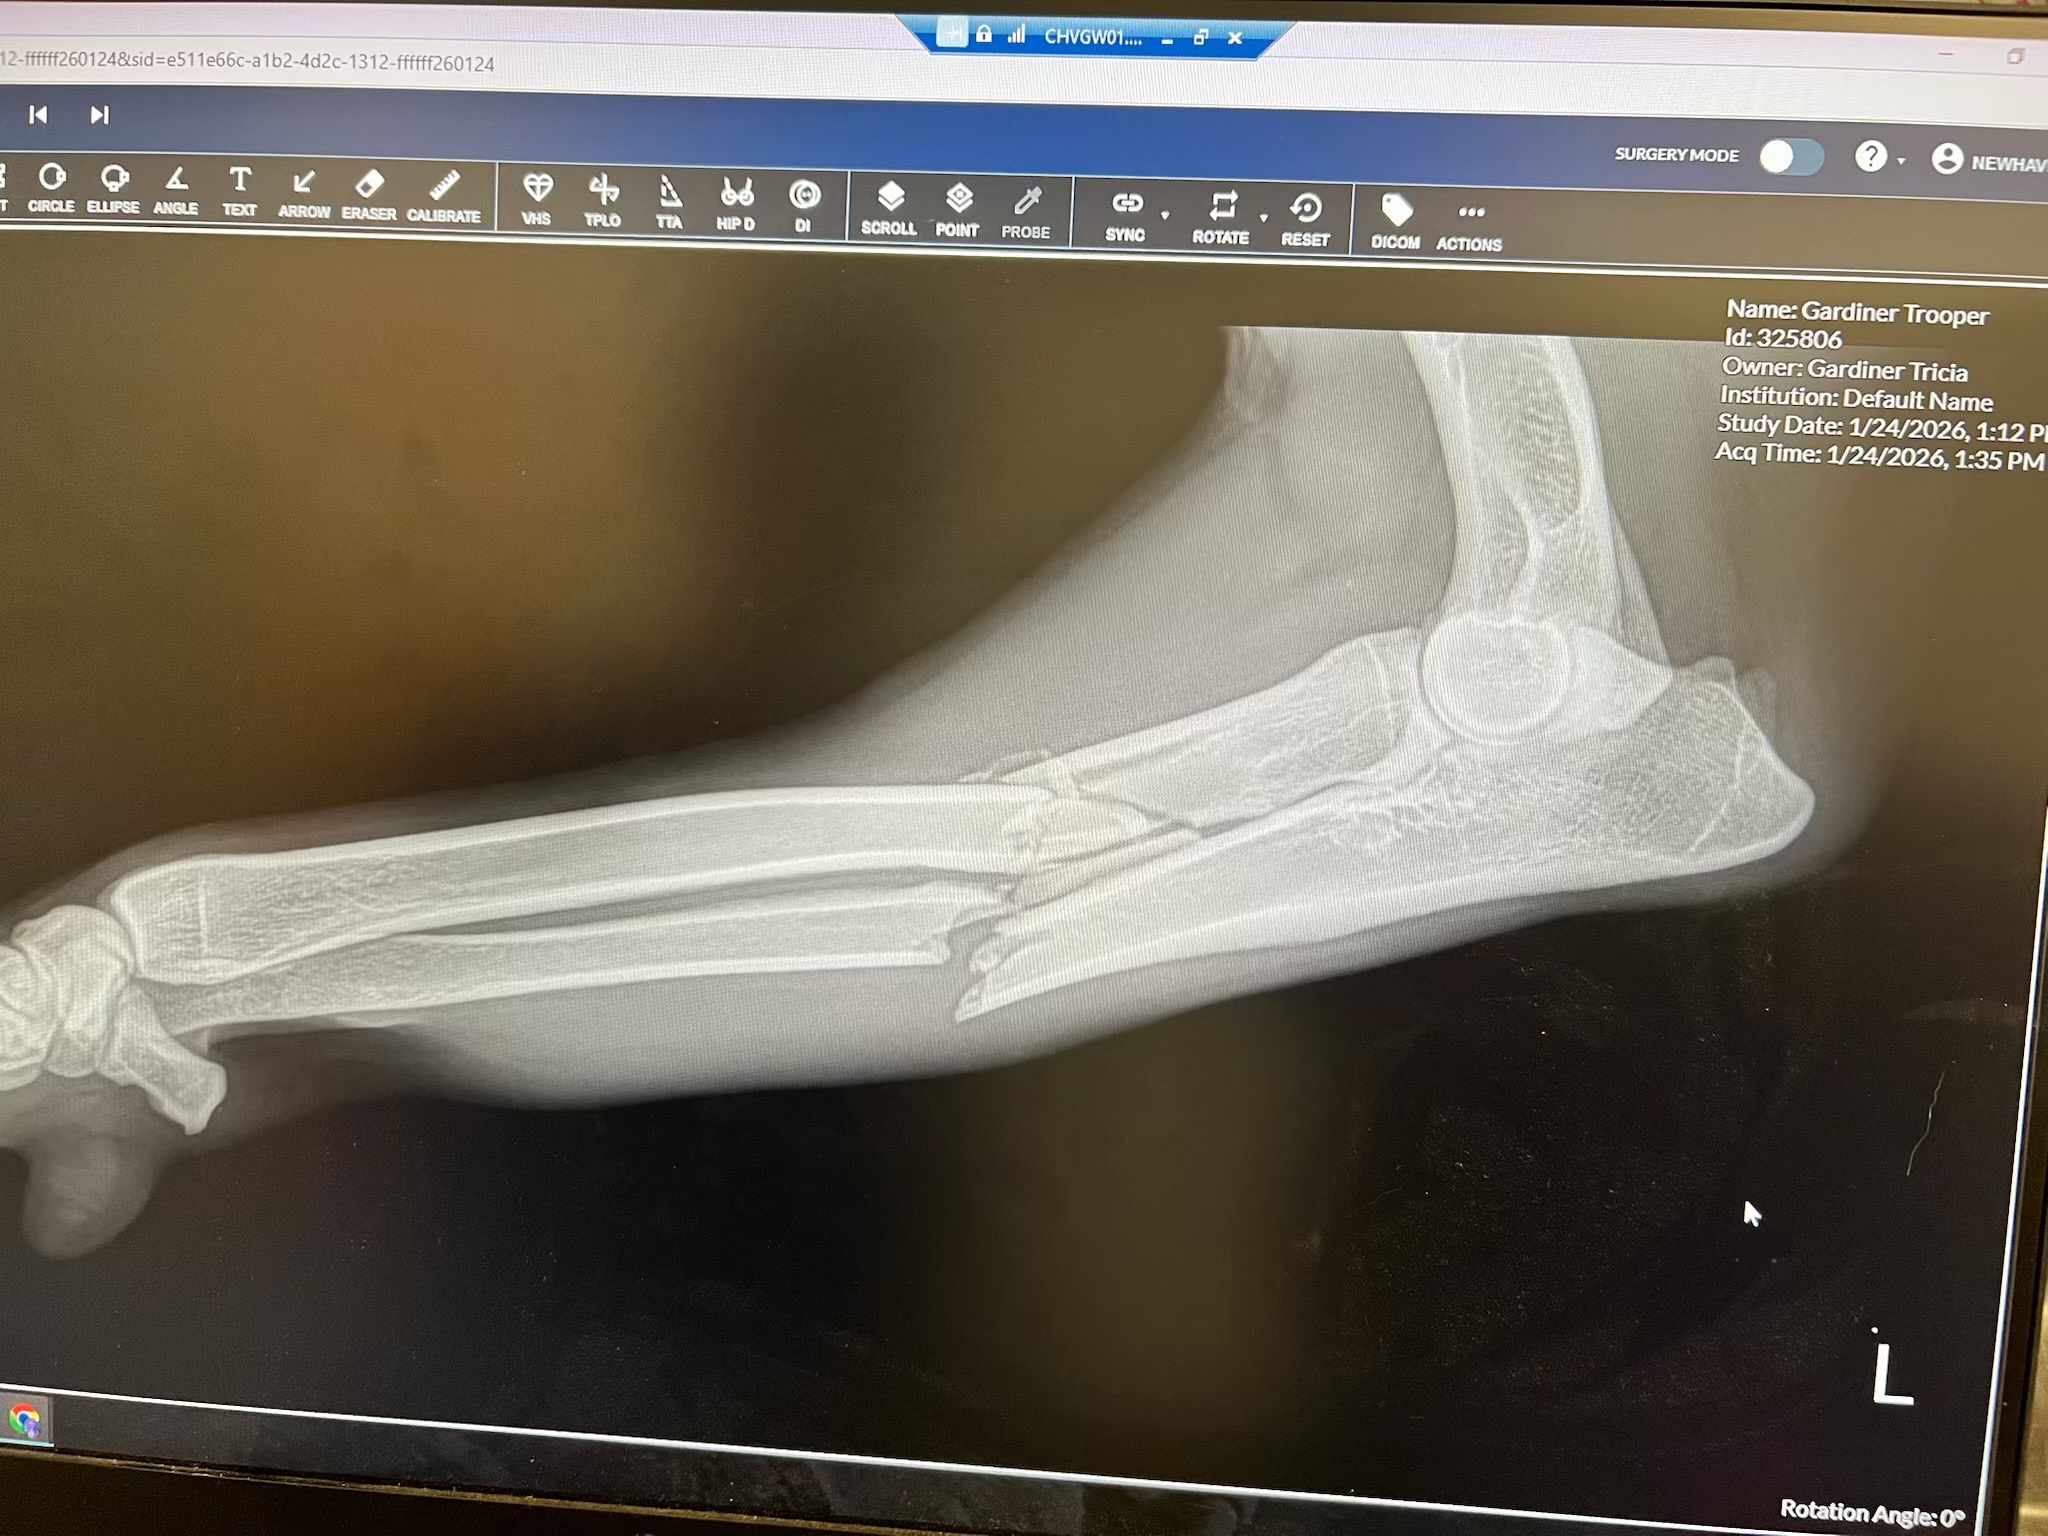

Our beloved boy, Trooper, was seriously injured in an accident and suffered a severe leg fracture. He’s in pain and needs urgent veterinary care and surgery to heal properly and avoid permanent damage.